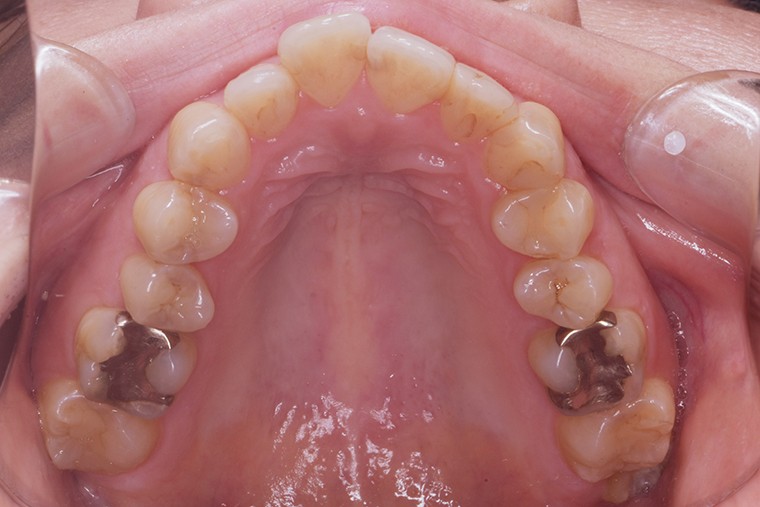

Case Study39歳女性ガタガタな歯のマウスピース矯正-矯正期間9ヶ月